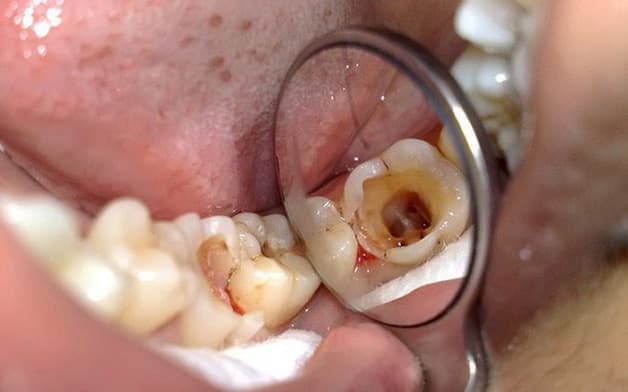

Sâu răng là hiện tượng xuất hiện lỗ hổng ở bề mặt răng, nếu như không được xử lý kịp thời, lỗ sâu có thể lây lan qua các răng xung quanh, gây triệu chứng đau nhức, khó chịu, thậm chí có thể dẫn đến những nguy cơ nguy hiểm như tiêu xương răng hoặc là mất răng.

– Sâu răng dẫn đến nguy cơ hoại tử tủy

Khi tình trạng viêm nhiễm ngày một nặng nề, cùng với đó, không thể áp dụng các phương pháp như trám răng hay bọc răng sứ thì lúc này nhổ răng là chỉ định hoàn toàn cần thiết để tránh tình trạng viêm nhiễm lây lan sang các răng khác. Thậm chí, nếu như không được điều trị triệt để còn có thể dẫn đến các tình trạng nguy hiểm như áp xe răng hay viêm xương hàm.